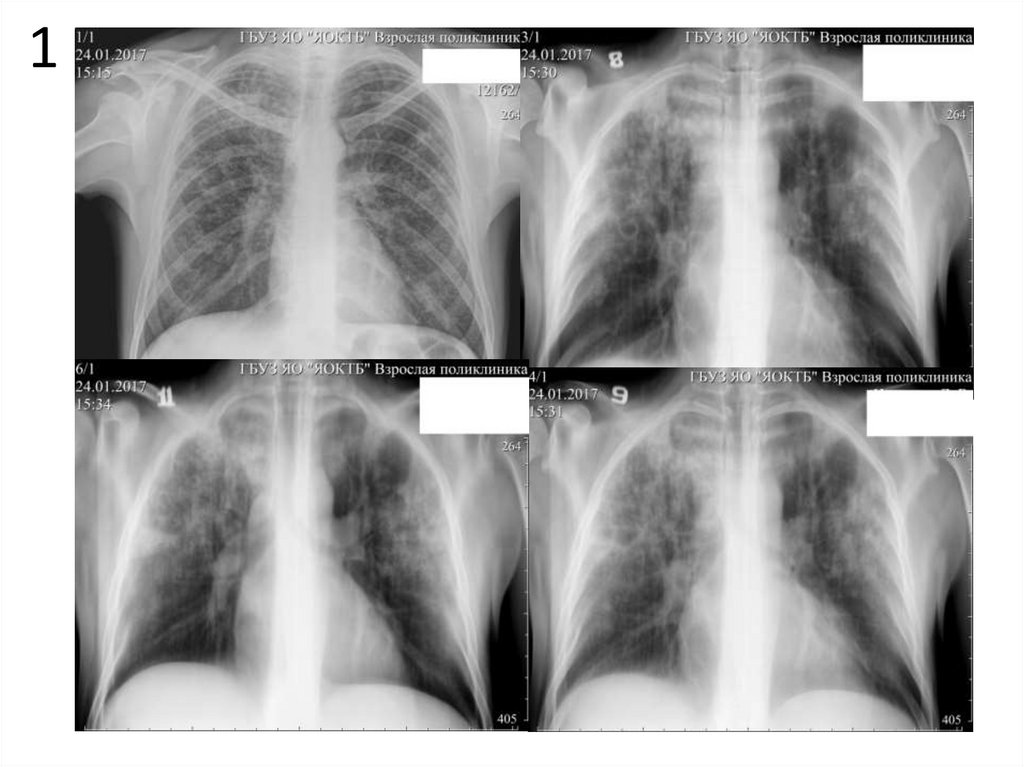

1

1. Опишите представленные снимки, выделите основной

рентгенологический синдром.

2. Имеются ли признаки туберкулеза на данных снимках?

Если да, перечислите их.

3. При наличии признаков туберкулеза определите форму,

фазу процесса, укажите возможные осложнения.